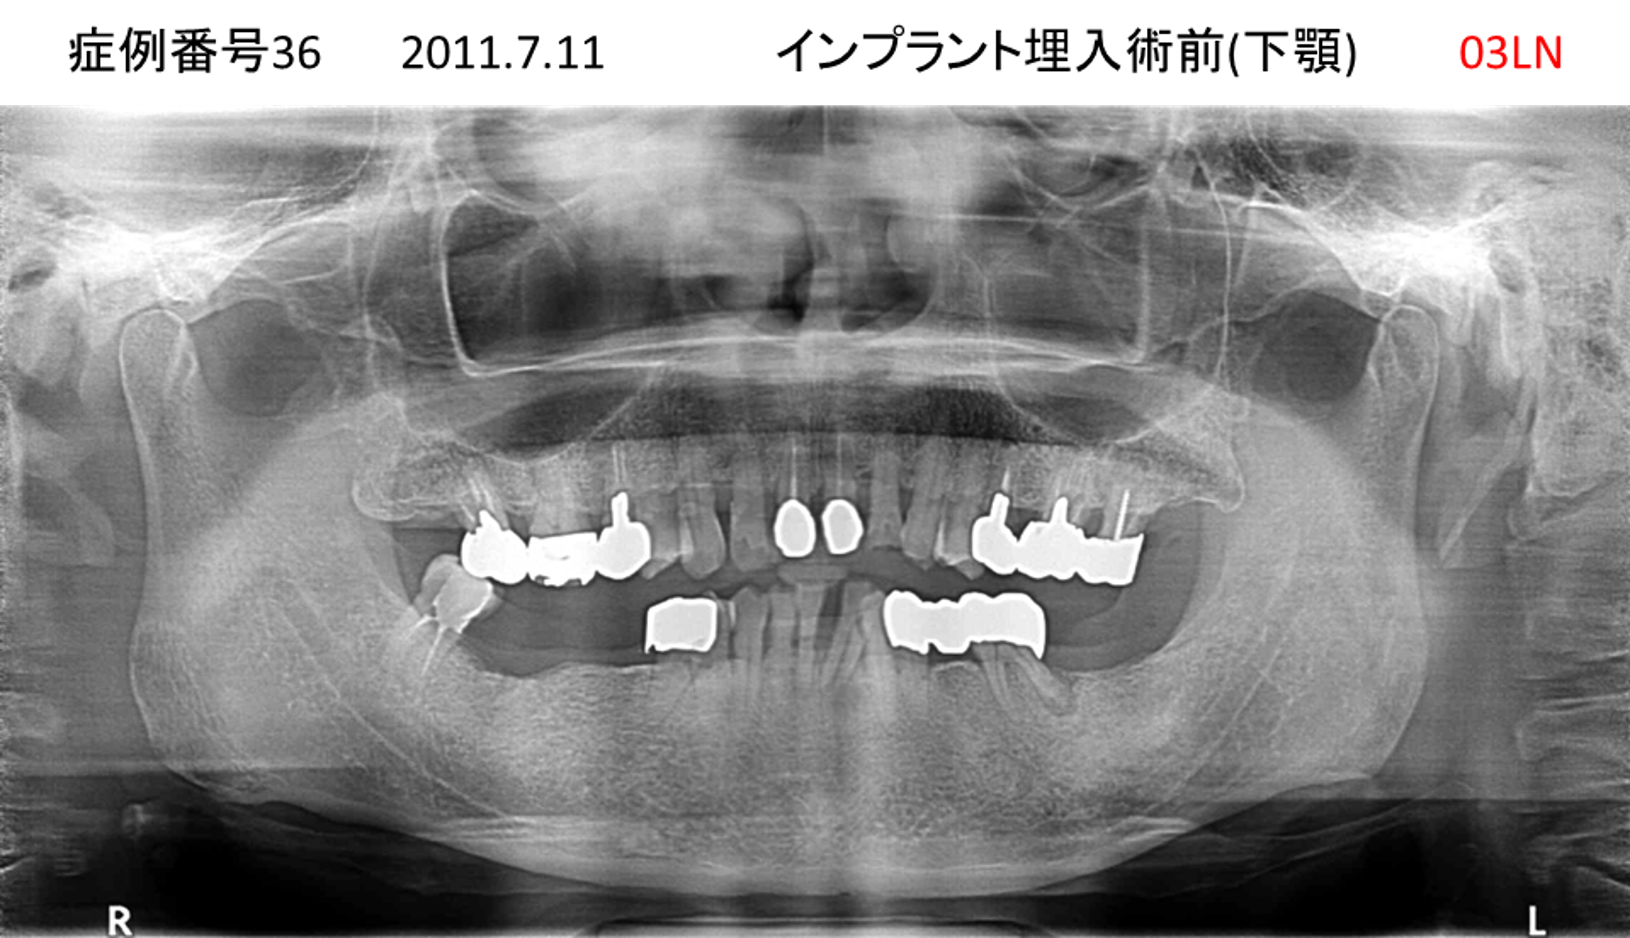

義歯が合わない、噛めない患者様のインプラント症例

| 治療名称 |

インプラントコーヌステレスコープ |

| 治療費用 |

270万円+税 |

| 治療期間 |

4か月 |

| 患者さんの症状(主訴) |

義歯が合わない、噛めない |

| 治療内容 |

インプラント、義歯作製(コーヌステレスコープ) |

| 治療結果 |

しっかり噛めるようになった。見栄えが良くなった。 |

| 治療の注意点(リスク/副作用) |

義歯が壊れた場合、インプラントが壊れた場合は再治療が必要 |